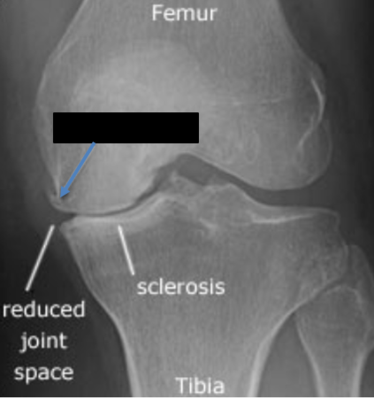

Which disease is shown

Answer

• Pagets

• OA

• RA